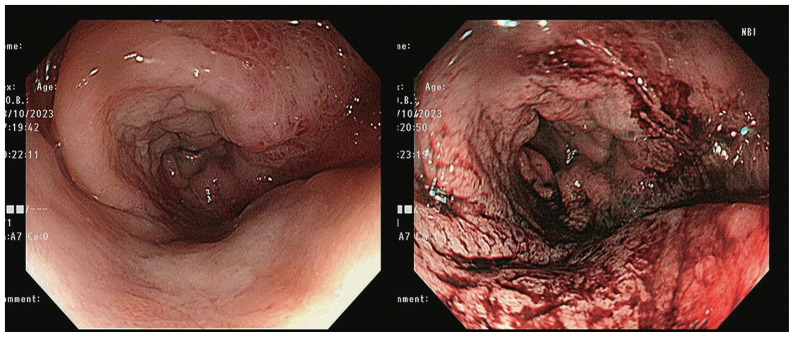

Breast cancer is the most common cancer among women worldwide. Breast cancer often metastasizes to the regional lymph nodes, bone, brain, liver, and lungs, whereas gastrointestinal tract metastases are rare. Herein, we present a rare case of rectal metastasis from breast cancer that occurred during palliative chemotherapy. A 69-year-old female with a history of invasive ductal carcinoma, negative for hormonal receptors and positive for human epidermal growth factor receptor 2 (HER2) receptor, underwent various treatments, including neoadjuvant chemotherapy, breast-conserving surgery, and adjuvant therapy. Eight months postoperatively, the patient experienced axillary lymph node recurrence, requiring palliative chemotherapy. Despite ongoing treatment, metastatic lesions were confirmed in the lungs and pleura. During palliative chemotherapy, the patient developed anal pain, and subsequent examination revealed an infiltrating rectal lesion. Despite histological confirmation of metastatic breast carcinoma and tubular adenoma, a multidisciplinary decision was made regarding palliative chemotherapy over surgical intervention. Eribulin was administered, but due to the patient's inability to tolerate the treatment, she passed away 3 months after rectal lesion diagnosis. Although breast cancer metastasis to the rectum is rare, clinicians should consider the possibility of rectal involvement and perform a digital rectal examination if anal symptoms are present.